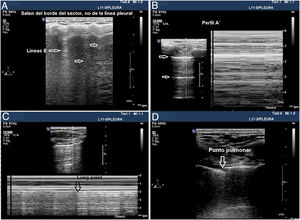

Aunque se pueda realizar un estudio sistemático en un paciente inestable en decúbito supino y dado que el aire tiende a ocupar la parte anterior del tórax, se debe comenzar explorando los campos anteriores. Una sonda lineal o microconvex es suficiente para el análisis de la línea pleural y para evaluar los artefactos pulmonares (fig. 4).

Signos en la ecografía pleural de barotrauma. A) Líneas E, artefacto vertical que no salen de la línea pleural en relación con enfisema subcutáneo. B) Patrón de líneas A y ausencia de deslizamiento pleural, que se confirma con el modo M, en la parte de la izquierda, que representa el signo de la estratosfera. C) Imagen confirmatoria de neumotórax y señala el punto de despegamiento de ambas pleuras visceral y parietal (lung point) en modo M. D) Imagen en 2D del punto pulmonar, zona de despegamiento de ambas pleuras.

Tres signos excluyen neumotórax20,30:

La presencia de deslizamiento (lung sliding) indica que ambas capas pleurales están en contacto, excluye neumotórax (VPN 100%) en el espacio donde el transductor está colocado. Sin embargo, su ausencia no lo confirma por su baja especificidad.

Visualizar una sola línea B indica que ambas capas están adheridas, lo excluye con VPN 100%. Mucha precaución en no confundirlas con las líneas E (líneas hiperecoicas verticales, que se inician en los tejidos blandos de la pared torácica en presencia de enfisema subcutáneo) (fig. 4A).

Presencia del signo del latido pulmonar (lung pulse): movimiento pulsátil de la línea pleural sincrónico con los latidos del corazón en ausencia de deslizamiento pulmonar indica que la pleura parietal y visceral están en contacto, pero la ventilación regional está alterada (por ejemplo, atelectasia) debido a que el aire entre las capas pleurales impide su transmisión.

- •

Deslizamiento pulmonar (lung sliding) abolido con presencia de líneas A (perfil A’ en el protocolo BLUE) (fig. 4B).

Localizar el punto de contacto entre el pulmón colapsado y la colección de aire del neumotórax (punto pulmonar o lung point) (fig. 4C y D). Es un signo dinámico que muestra la alternancia de deslizamiento normal y abolido durante la ventilación en 2D o por la sucesión de imágenes normales (signo de la orilla) durante la inspiración y líneas horizontales (signo de la estratosfera o código de barras) durante la espiración en modo M. Es un signo específico con una sensibilidad del 66% y una especificidad del 100% para diagnosticar neumotórax30. Cuanto más lateral e inferior está el punto pulmonar en la pared torácica, mayor es su extensión. Un punto pulmonar muy posterior o ausente sugiere un neumotórax masivo con atelectasia completa del pulmón31.